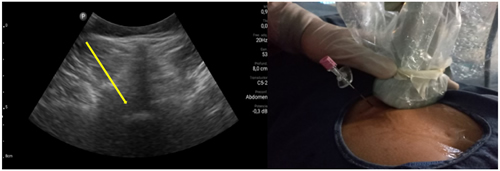

Pacientes y métodos: Un total de 25 pacientes con dolor radicular lumbosacro fueron seleccionados para recibir inyecciones epidurales interlaminares de esteroides en posición decúbito dorsal, utilizando la técnica ecoguiada en plano, en tiempo real, en eje corto o transversal. En todos los casos, un epidurograma de control fue realizado previo a la inyección de la solución de esteroides. El rendimiento de la técnica fue estudiado mediante la tasa de éxito de la misma, entendido como éxito a la obtención de un epidurograma sin necesidad de abandonar la técnica ecográfica en un tiempo menor a 10 minutos. El rendimiento del procedimiento fue estadísticamente evaluado por el método de la suma acumulativa (CUSUM), y la curva de aprendizaje aplicando este método fue construida.

Figura 2